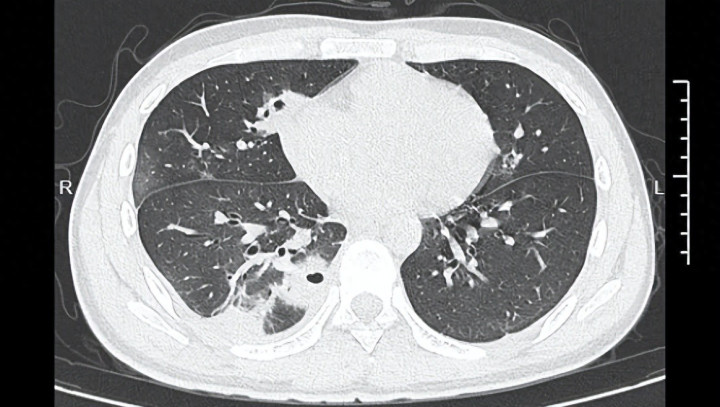

熬到第三天,小林照旧烧到39℃,迅速去病院就诊。CT搜检成果涌现:小林的肺里有十几个空泛,部分肺组织照旧坏死,这是典型的血源性肺脓肿。

小林的CT影像涌现肺里有多个空泛